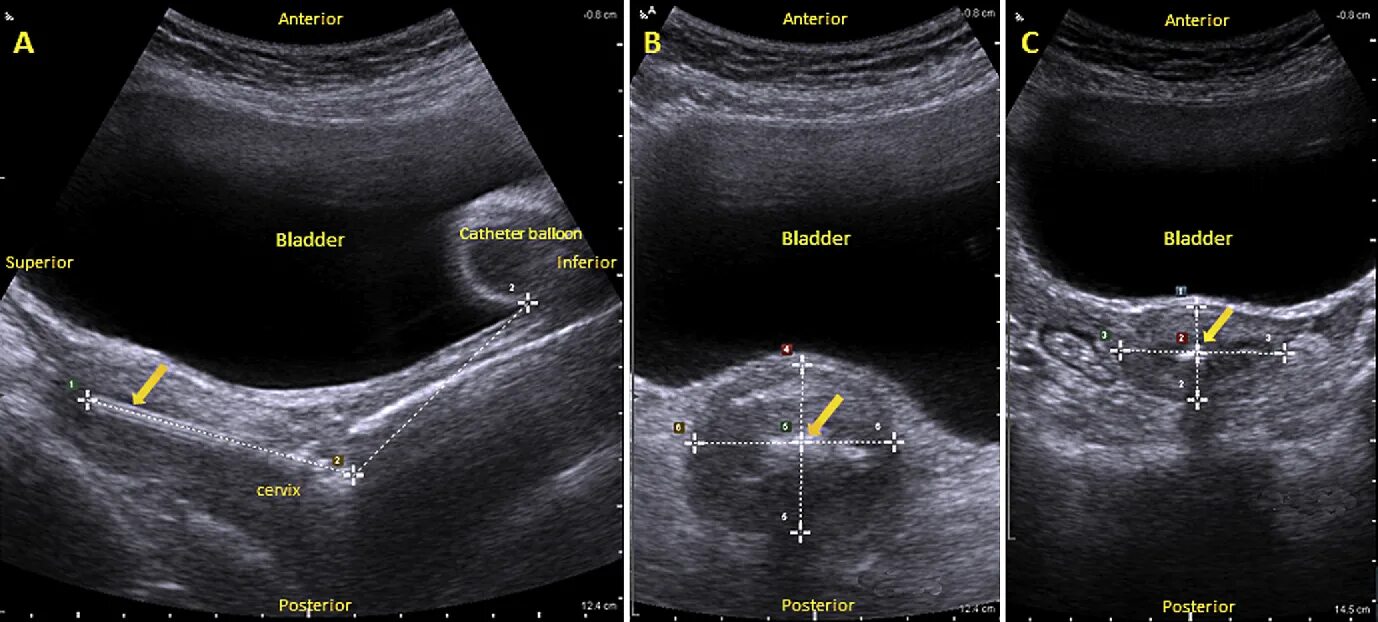

Ретрофлексия матки что это такое